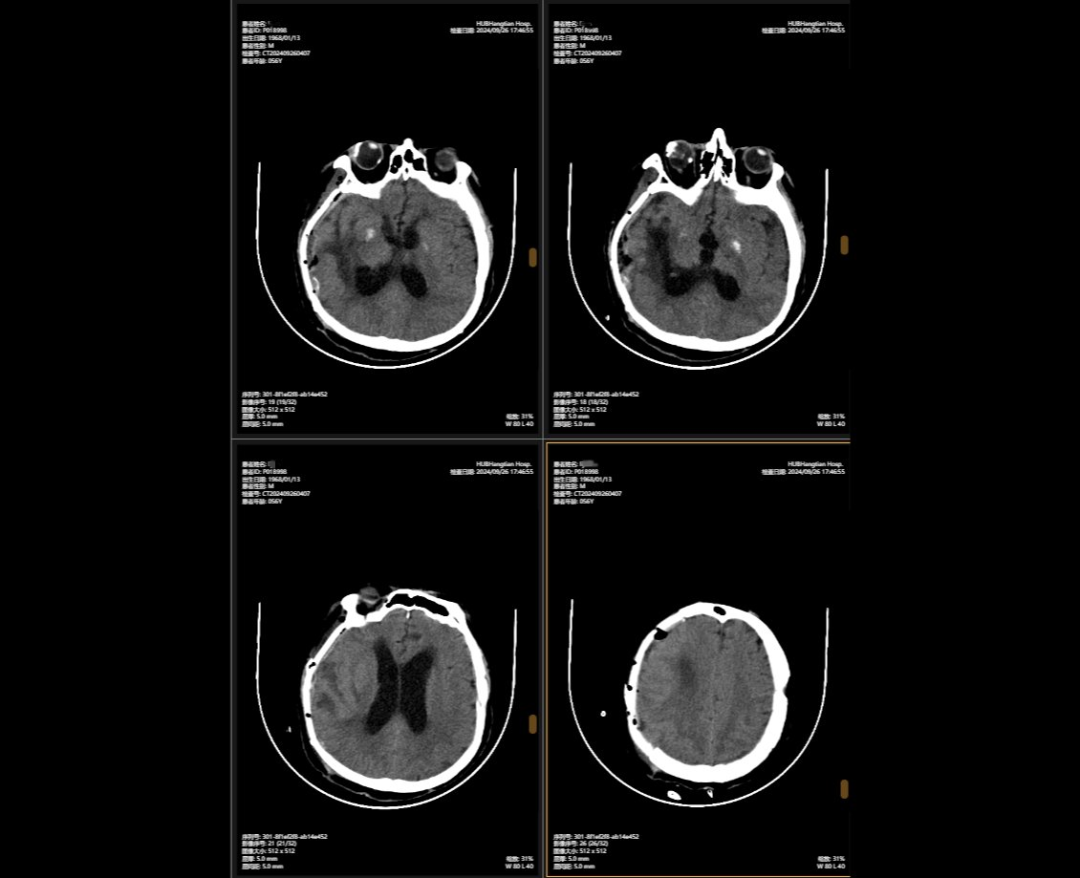

2024年5月,56岁的李先生(化名)不幸遭遇严重车祸。他当场陷入昏迷,生命垂危。他被送往湖北航天医院后,检查结果让所有人忧心忡忡:他头部被击中,不仅多处出血,脑组织挫伤,连呼吸和心跳的“总司令部”脑干也受伤。此外,还有头骨、颈椎和多处肋骨骨折,情况危急。 李先生头部多处受伤,就像一颗“炸弹”,随时可能有生命危险。航空医疗神经外科团队接到诊断后,面对如此复杂的颅内损伤,神经外科主任陈义勇做出了紧急决定。他一方面精心准备手术,另一方面迅速展开多学科会诊。多学科团队集结容易出血,反复讨论,制定了详细的手术方案。确定手术方案后,神外团队争分夺秒为李先生进行了多发颅内血肿清除+右侧开颅颅内减压+去骨瓣切除+左侧硬膜外血肿清除+矢状窦破裂止血。手术中,医生进行了精准手术,成功止血,最大限度地保护了正常脑组织,给了李先生生存的希望。 然而,成功的手术是生存的第一道障碍。手术后,李先生陷入昏迷,并出现意识不清、脑积水等新的健康危机。 在重症监护室(ICU)内,内科神经外科团队和内科ICU团队自发组成了轮换团队。他们24小时守候在李先生的床边,监测监护仪上的数据波动,实时调整用药方案。根据病情变化,戴上呼吸机,进行早期康复刺激。他们的努力和坚持每天早上和下午结合在一起,就静静地倒下了。 这是一场与死亡的拉锯战,由李先生内心的忠诚和医护人员的不懈努力推动。幸运的是,李先生的生命体征逐渐稳定,他们才得以幸存。 李先生病情稳定后,团队紧张的神经终于放松下来。他们立即为他制定了颅骨缺损和脑积水的治疗方案。 2024年9月,李先生接受了颅骨重建手术,“修复”了之前切除的颅骨缺损。颅骨保护大脑,解决颅内压不稳定的问题。手术后,她的神经症状明显改善。三个月后,申外团队继续进行脑室腹腔分流手术。植入分流管后,脑积水问题就这么解决了活了,脑压恢复正常。 颅骨固定手术前后对比 经过两次手术,李先生的生命力逐渐被点燃,他从深度昏迷中慢慢苏醒。 起初,他只能靠在病床上眨着眼睛,简单地向身边的医护人员传达自己的需求。 2025年2月,他的意识逐渐清醒。 “当李老师第一次让我带笔记本,看着他在笔记本上认真地一笔一笔写下的时候,我就知道这份责任是值得的,生命的力量超乎我们的想象。”神经外科护士刘倩说。 后来,在李先生的不断努力和医疗团队的坚持下,这一生的光芒越来越亮:在接受神经康复治疗的同时,“他开始靠墙独自站立一分钟。到了3月份,他甚至可以给我一个魔方来锻炼他的大脑,他还拿了一个魔方来锻炼他的大脑。”“锻炼身体,认真探索,玩俄罗斯方块之类的智力游戏。”医生说,这是锻炼计算技能的好方法。李先生的家人多次表示,他的每一步发展,从苏醒到意识清醒,文字表达能力的恢复,认知功能、计算能力、长期记忆的恢复,都凝聚着医护人员的智慧和汗水,也闪耀着李先生和家人永不放弃的信念之光。 经过300个日日夜夜,2025年2月底,神经外科团队对李先生的病情进行了全面的检查和评估。检测结果显示,李先生恢复良好,符合出院标准。 目前,李先生仍然偶尔去航空医学科接受康复训练。在神经外科团队和康复治疗团队的配合下,他的行走稳定性、言语清晰度和短期记忆能力得到了改善。持续改善。据家人介绍,“爸爸现在能独立行走,能照顾自己的起居了,这让我们感觉好多了。” (通讯员 刘谦)